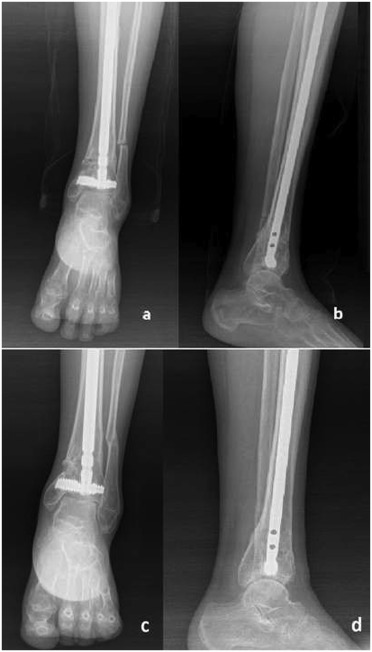

A 49-year-old man suffered a traffic accident. He had an AO type A2-3 fracture of the tibia with no additional injury. He had been operated in a different clinic with Kirschner wires. Three months after the first operation, revision was made with an Ilizarov external fixator and followed up for 7 months at the same clinic. The patient was admitted to our clinic with complaint of pain, inability to walk, and limited ankle movement. Anteroposterior (AP) and lateral ankle X-rays were obtained (Fig. 2 a and b). Malunion and severe complex regional pain syndrome with deformity were diagnosed.

Fig. 2.

Preoperative AP (a) and lateral (b) , and postoperative AP (c) and lateral (d) X-rays of Patient 1.

A varus producing close-up osteotomy was performed. A 40 × 8-mm DSBLS was inserted parallel and 4 mm above the ankle joint. Two osteotomies were constructed to produce a 12° wedge, which was then removed. The distal osteotomy was 22 mm proximal to the ankle joint. There was nonunion of the fibula at the level of center of rotation of angulation, so that osteotomy was not required for the fibula. Following removal of the wedge, the cut surfaces were opposed, and a 360 × 1-mm nail was inserted through the distal face and interlocked. After interlocking, alignment was reassessed by using the calcaneocrural angle under fluoroscopy. The correction was controlled with postoperative AP-lateral X-rays (Fig. 2 c and d).